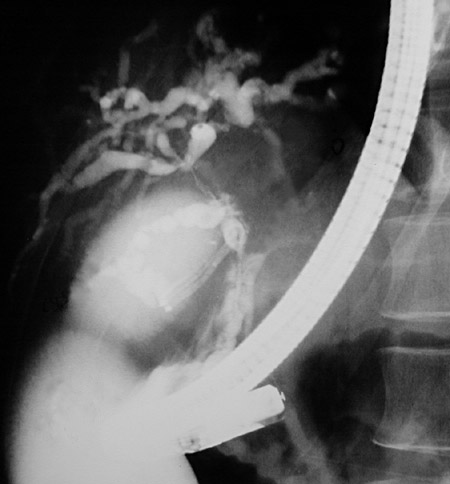

| This radiograph was taken at the time of an endoscopic retrograde pancreatography (ERCP) procedure to reveal areas of marked segmental narrowing of the common bile duct along with the common hepatic duct in a case of sclerosing cholangitis. The cystic duct and the gallbladder are seen toward the left side of this image. Some cases of sclerosing cholangitis are seen in association with idiopathic inflammatory bowel disease (Crohn disease or ulcerative colitis). |